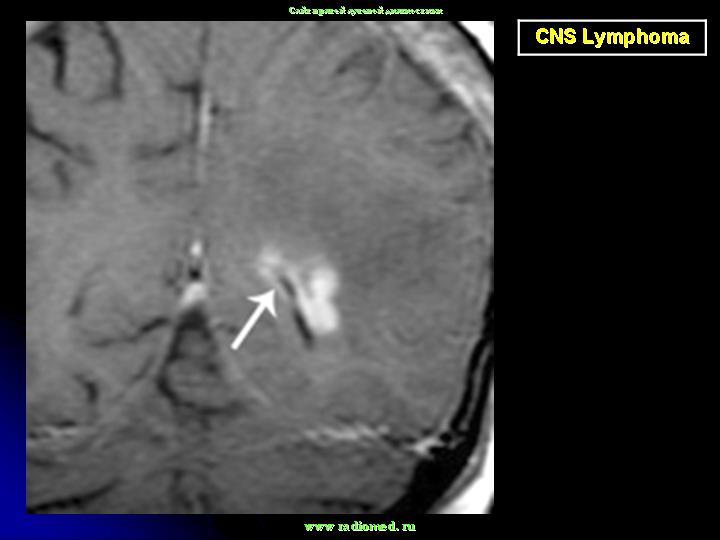

Диагноз подозревается на основе изображений КТ и МРТ.

Лимфома.